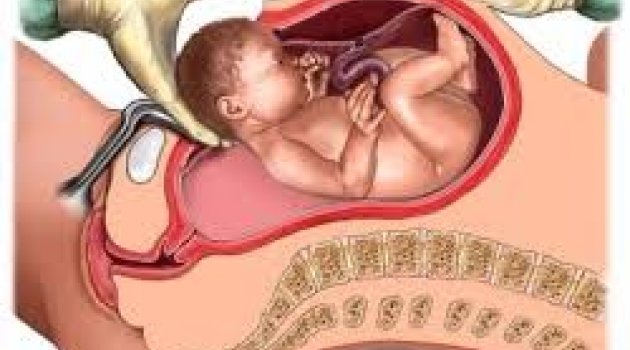

Bebeğin doğum anı

Bir bebek nasıl dünyaya geliyor? Normal doğum nasıl gerçekleşiyor? Bebeğin doğum anı ile ilgili merak ettiğiniz her şey bu videoda!

Bebek doğum videosu izlemek için tıklayın!